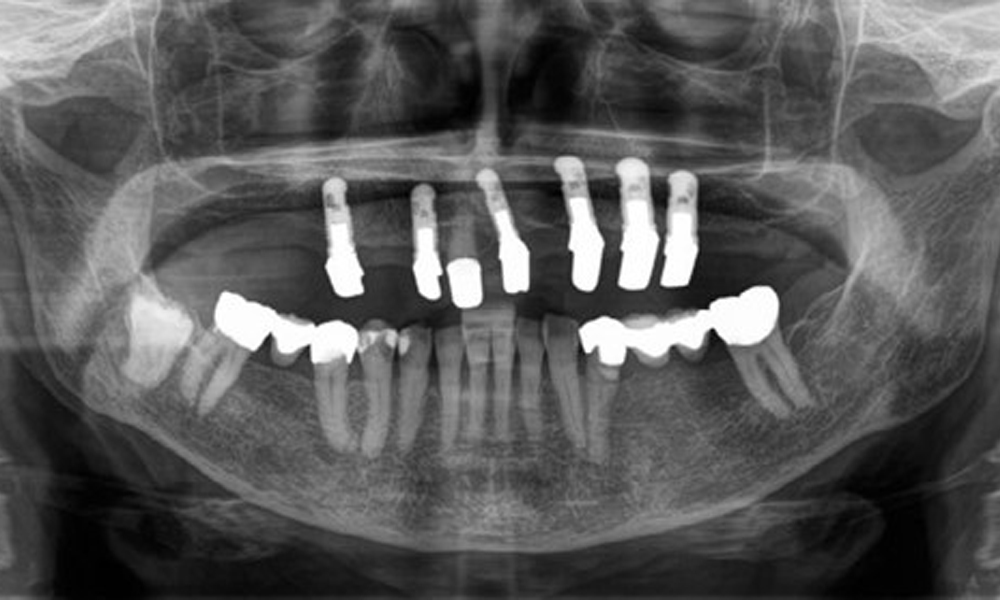

The radiological findings show partially edentulous dentition with maxillary implants for teeth 15, 13, 21, 23, 24, 25 and a telescopic crown on tooth 11. Adequate mandibular bridges spanning 37 to 34 and 45 to 47 are present. 48 is impacted. There are suspected secondary caries distally on 43 and mesially on 44. 44 is restored with a non-radiopaque cavity lining. There is generalised horizontal bone loss of approx. 10% to 30% and localised vertical bone loss affecting teeth 22 and 42 (Fig. 5).